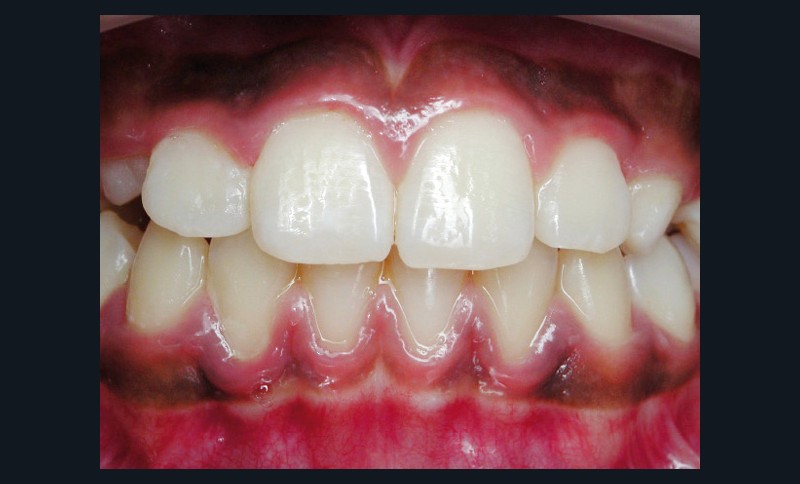

La parodontite chronique est une maladie inflammatoire d’origine bactérienne, dont la prévalence est très élevée. Bien que les progrès des thérapeutiques soient nombreux et concernent un nombre important de traitements parodontaux, la thérapeutique étiologique non chirurgicale reste le traitement initial de choix des parodontites. Elle comprend un enseignement à l’hygiène orale et un débridement mécanique du biofilm bactérien, à l’aide d’ultrasons ou de curettes. L’antibiothérapie systémique n’est pas systématique, mais est indiquée dans les cas les plus sévères. Souvent, la seule thérapie mécanique se montre efficace et suffisante pour obtenir des améliorations cliniques très significatives. Cependant, elle a aussi des limites, et certains sites d’accès délicats nécessitent alors une thérapeutique chirurgicale complémentaire. Enfin, la stabilisation de la situation à long terme ne peut être obtenue que si une maintenance rigoureuse et régulière est mise en place(fig. 5 et 6).